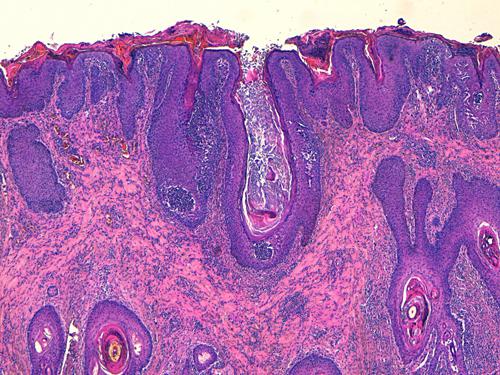

Photo 1 (Hémalun Eosine X 40) peau velue: L’épiderme et les infundibula folliculaires

sont hyperplasiques et hyperkératosiques. Les infundibula folliculaires sont le siège de pustules luminales et

pariétales, avec des fissurations linéaires parallèles au grand axe des follicules.

Le derme montre un inflammation péri-vasculaire et folliculo-centrée à diffuse.

Légendes de la Photo 1 :

- Double flèche bleue pointillée : grand axe des infundibula folliculaires à gaine épithéliale hyperplasique

- Double flèche verte : derme

- Ovales jaunes : pustules dans la paroi des follicules pileux

- Flèches jaunes : fissures linéaires dans la paroi des follicules pileux qui sont parallèles au grand axe des infundibula folliculaires

- Étoiles vertes évidées : lumière d’un follicule pileux hyperkératosique occupée par de la kératine et couche cornée hyperkératosique

- Étoiles rouges pleines : infiltrat dermique périvasculaire, périannexiel à diffus

- Étoiles turquoises pleines : lumière de follicules pileux obstruée de débris inflammatoires